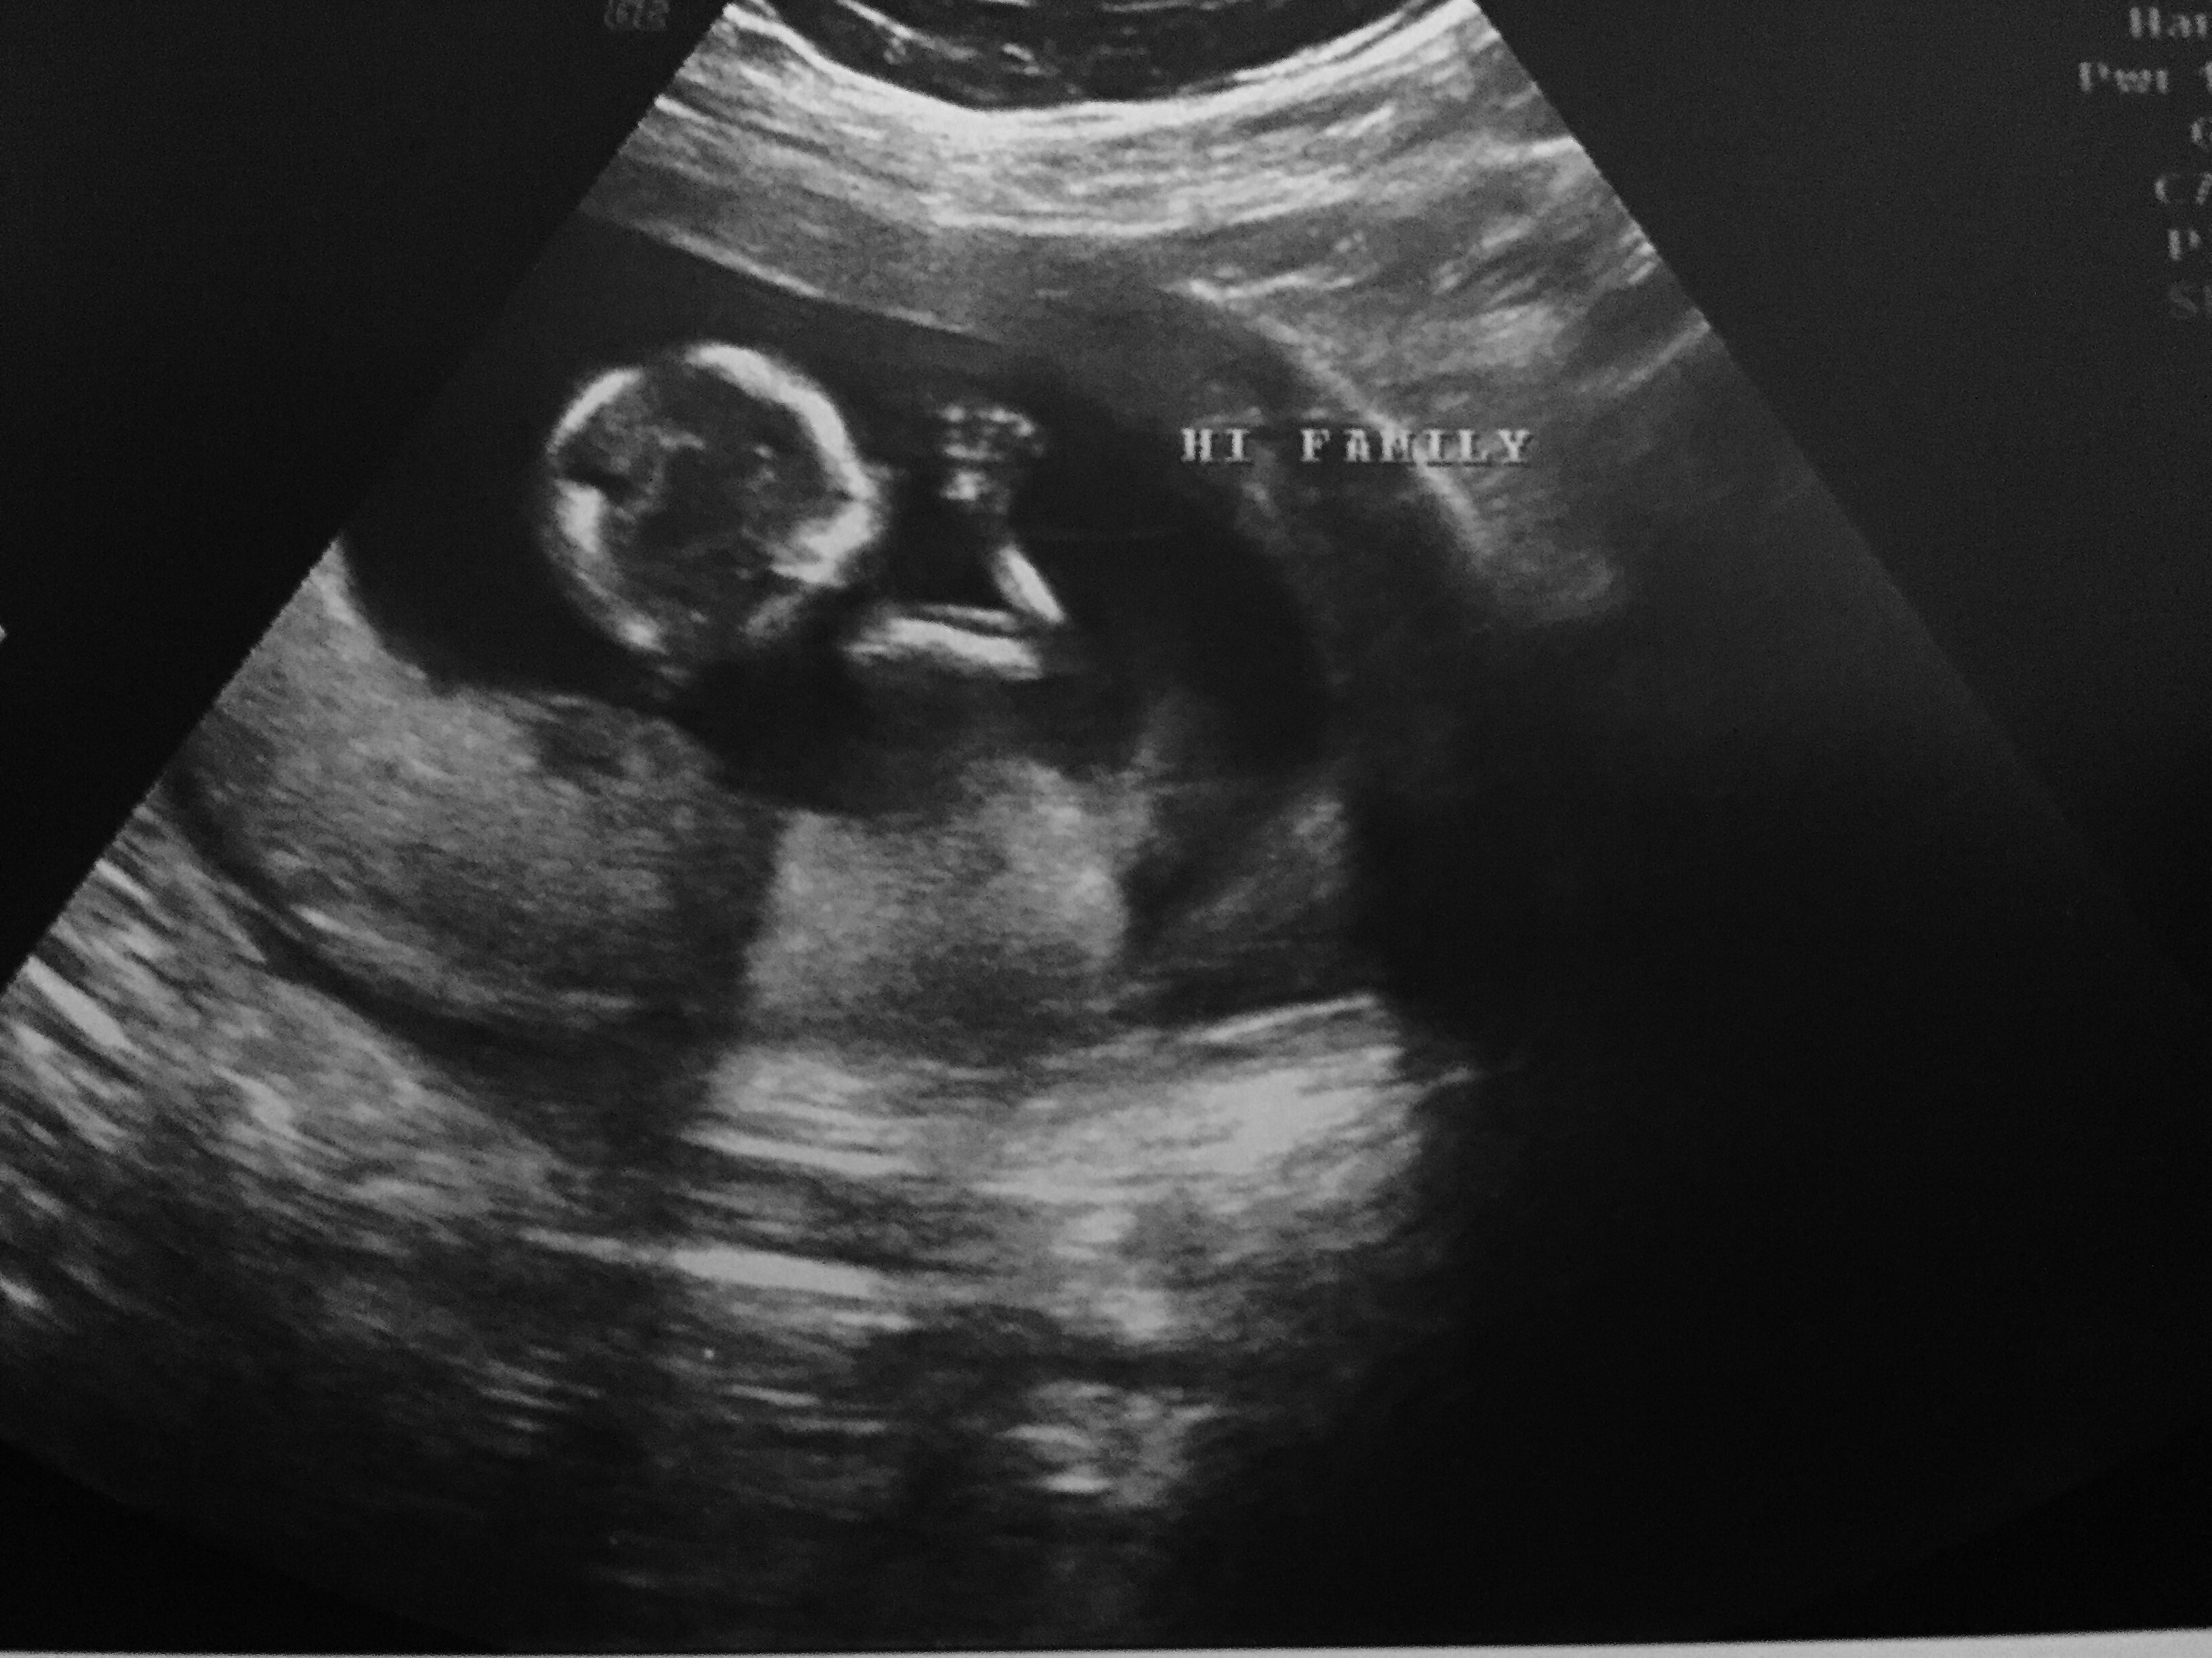

Got a surprise ultrasound today at 14w1d- thought we were just going to hear the heartbeat but we got pics too! Last time was at 9 weeks and she looked like a white smear on the U/S. Now look! So exciting!!